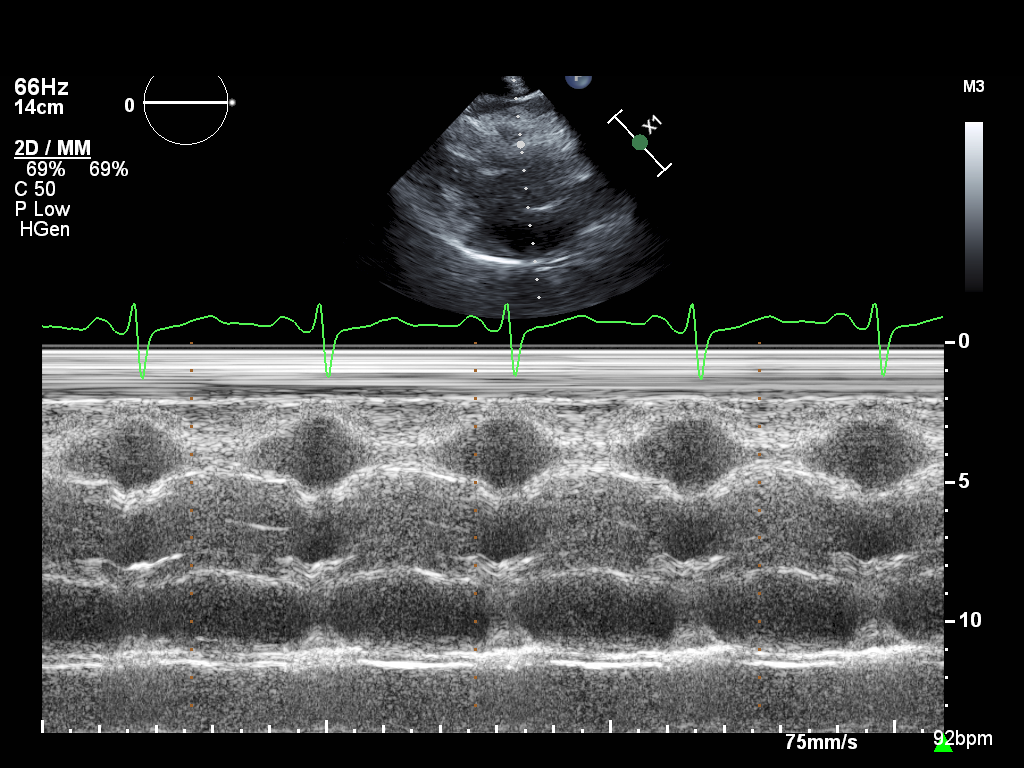

M-mode (5 views)

ImageView NameDescription

mmode-a4ch-rv mmode-a4ch-rv M-mode for measuring TAPSE

mmode-ivc mmode-ivc M-mode of the inferior vena cava

mmode-plax-av mmode-plax-av M-mode of the aortic valve in PLAX

mmode-plax-lv mmode-plax-lv M-mode in PLAX focused on LV walls

mmode-plax-mitral mmode-plax-mitral M-mode in PLAX focused on the mitral valve